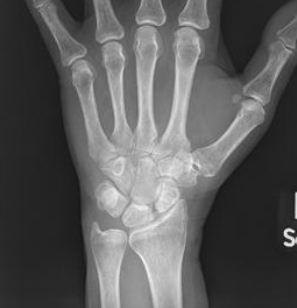

What are seen on xray for a SLAC stage 3 wrist?

Pa radiograph